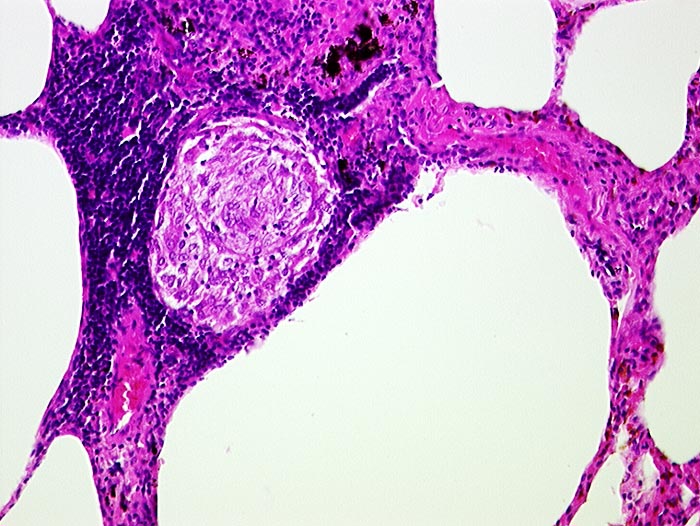

PathoPic ID 708 - Sarkoidosegranulom

Sarkoidosegranulom

Entzündung / Reparatur

Lunge

Lunge, Mediastinum mit Thymus

Granulom aus Epitheloidzellen umgeben von Lymphozyten in einem Alveolarseptum.

Granulome in Lungen, Bronchialschleimhaut, Leber, Milz und Lymphknoten pulmonal

Histologie